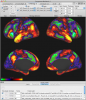

Connectome Workbench Images

3 Images available.

Description:Functional connectivity viewing in Workbench

(click to enlarge)